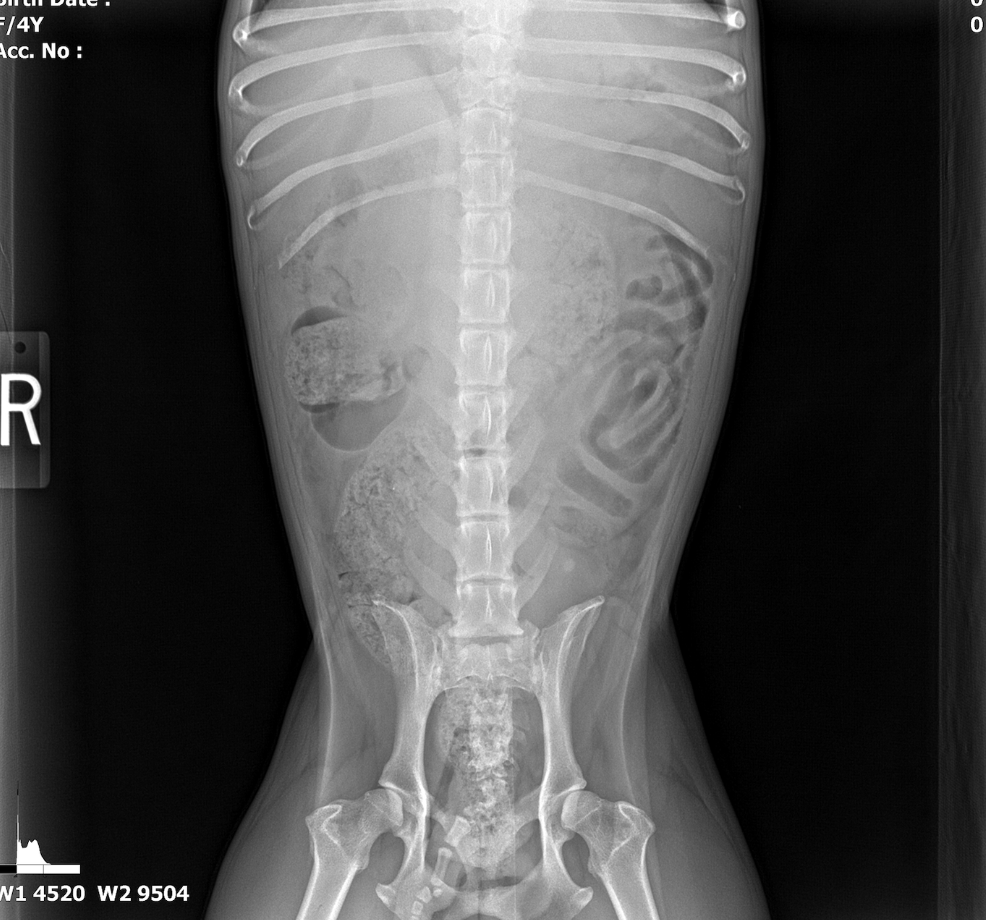

The patient was referred from another veterinary clinic for advanced imaging following the identification of a suspected abdominal mass on radiographs. Ultrasonographic evaluation revealed a splenic mass consistent with an abscess, from which purulent fluid was aspirated and drained. A splenectomy was scheduled for later the same day.

The spleen revealed an expansive parenchymal mass that measured 10+ cm without evidence of cavitation. Hyperechoic fat was noted around the spleen. This is consistent with inflammation.

A slight amount of free fluid was noted.

- Splenic mass.

There was no obvious evidence of metastatic disease. Proactive splenectomy, liver inspection and biopsy was indicated. Rapid echocardiogram was recommended if not already performed to ensure that metastatic disease was not present. Differentials included benign hyperplasia, hemangiosarcoma and round cell neoplasia. However, the mass was highly precarious and at risk for rupture.